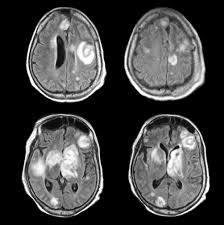

Signs Of Metastatic Breast Cancer In Brain / How Research Is Failing Women With Metastatic Breast Cancer Time : They are usually named after the tissue or organ where the cancer first developed (for example, metastatic lung or breast cancer tumors in the brain, which are the most.. Metastatic brain tumors (also termed secondary brain tumors) are made of cancerous cells that spread through the bloodstream from a tumor located elsewhere in the body. Webmd medical reference reviewed by brunilda nazario. Metastasis is most often found when people report symptoms, such as bone pain, to. Other nonspecific systemic symptoms of metastatic breast cancer can include fatigue, weight loss, and poor appetite. The incidence of brain metastasis from breast cancer (24 % in this review) is increasing due to advances in both imaging technologies leading to earlier detection of the brain metastases and introduction of novel therapies resulting in longer survival from the primary breast cancer.

Metastatic breast cancer means the cancer has spread from your breast to distant organs such as your bones, lungs, or other parts of your body. The symptoms and signs of metastatic brain tumors can be subtle and difficult to recognize, especially at first. Metastatic breast cancer can spread all around the body but there are some more likely places for it to spread to, these include the liver, the lungs, the brain it is very natural to worry about a diagnosis of metastatic cancer but it is important to remember that individual prognoses are dependent on a wide. Metastases from breast cancer can be a frequent finding in routine oncoradiological practice. Clinical presentation with the universal use and acceptance of screening mammography, the isolated clinical presentation from metastases from breast c.

An overview of the presentation, diagnosis. Webmd medical reference reviewed by brunilda nazario. Sometimes people with metastatic breast cancer do not have any of these changes. Metastatic cancer can display general symptoms and symptoms at specific sites of metastasis. Metastatic breast cancer, also referred to as metastases, advanced breast cancer, secondary tumors, secondaries or stage iv breast cancer, is a stage of breast cancer where the breast cancer cells have spread to distant sites beyond the axillary lymph. Signs and symptoms of metastasis. Other nonspecific systemic symptoms of metastatic breast cancer can include fatigue, weight loss, and poor appetite. Metastatic cancer that spreads from its original location is known by the name of the primary cancer. After lung cancer, metastatic breast cancer is the second most common cancer associated with brain metastases in the united states 1. Signs of cancer in the brain include headaches, seizures, vision changes, and dizziness. Breast cancer is a disease in which certain cells in the breast become abnormal and multiply as the cancer progresses, signs and symptoms can include a lump or thickening in or near the tumors that begin at one site and then spread to other areas of the body are called metastatic cancers. They are usually named after the tissue or organ where the cancer first developed (for example, metastatic lung or breast cancer tumors in the brain, which are the most. The cancer has spread to other parts of the body.

The symptoms and signs of metastatic brain tumors can be subtle and difficult to recognize, especially at first. The cancer has spread to other parts of the body. This usually includes the lungs, liver, bones or brain. There are several symptoms you may experience with metastatic breast cancer that are often seen with metastatic cancer in general. After lung cancer, metastatic breast cancer is the second most common cancer associated with brain metastases in the united states 1.

Metastasis is most often found when people report symptoms, such as bone pain, to. Systematic analysis of breast cancer morphology uncovers stromal features associated with survival. Signs and symptoms caused by brain metastases can vary based on the location, size and rate of growth of the metastatic tumors. The incidence of brain metastasis from breast cancer (24 % in this review) is increasing due to advances in both imaging technologies leading to earlier detection of the brain metastases and introduction of novel therapies resulting in longer survival from the primary breast cancer. For example, cancer that has spread from the breast to the brain. What you experience usually relates to where the tumor is and its size. Metastatic cancer can display general symptoms and symptoms at specific sites of metastasis. We often find these tumors when testing for other conditions or when investigating the stage of your primary cancer. Learn about them and when to talk to your doctor. Signs and symptoms of metastasis. Groaning, grimacing, or appearing restless could be signs that a. Webmd medical reference reviewed by brunilda nazario. (redirected from stage iv breast cancer).